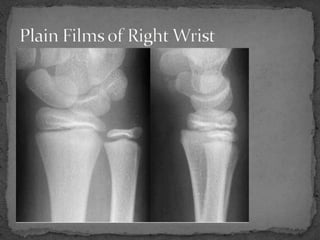

A 9 year old female presented to the emergency department after falling from a horse at summer camp and injuring her right wrist. She complained of pain with palpation and movement of the wrist. Examination revealed mild swelling and tenderness over the wrist, but plain films did not show any obvious abnormalities. Due to the possibility of a Salter Harris I fracture that may not be visible on initial x-rays, the patient was splinted and advised to follow up with orthopedics in 7-10 days for repeat films to check for any delayed findings.